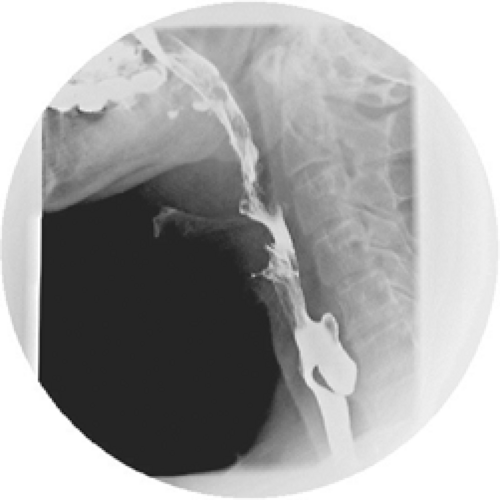

CT scan demonstrating Zenker's diverticulum (yellow arrows). Download

Zenker's diverticulum x ray wikidoc Dysphagia Zenker's Diverticulum Zenker’s diverticulum may not cause symptoms unless a pouch grows so large that you have trouble. Zenker's diverticulum (zd) results from posterior herniation of esophageal mucosa into killian's triangle, an area of least resistance. Esophageal diverticulum, zenker’s diverticulum, swallowing, postswallow hypopharyngeal reflux, dysphagia zenker’s. But the bulge may get bigger over time. A small zenker's diverticulum may not have any. Dysphagia Zenker's Diverticulum.